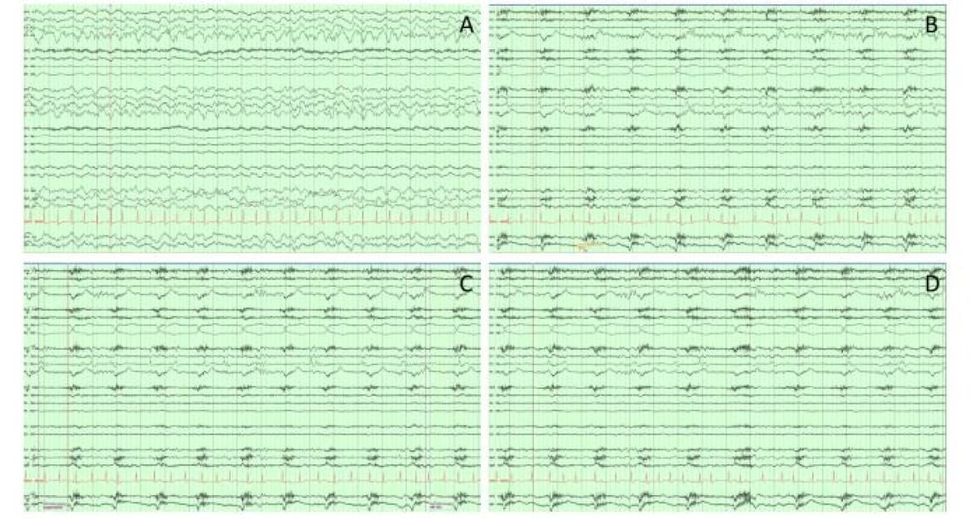

Gjatë njërit prej skanimeve, pacienti papritur pësoi një atak kardiak dhe ndërroi jetë, gjë që u mundësoi mjekëve dhe studiuesve të regjistronin për herë të parë aktivitetin e trurit para, gjatë dhe menjëherë pas vdekjes.

Të dhënat, përfshirë 30 sekondat para dhe pas ndalimit të rrahjeve të zemrës, u analizuan nga një ekip në Vankuver, i udhëhequr nga doktori dr. Ajmal Zemmar. Rezultatet ishin befasuese! - transmeton Telegrafi.

Në fakt, teoria e vjetër sipas së cilës i gjithë jeta i “shfaqet para syve” njeriut në çastin e vdekjes, ndoshta nuk është vetëm mit. Regjistrimet e trurit treguan përforcim të “oscilacioneve gama”, valë të trurit të lidhura me rikujtimin e kujtimeve dhe ëndërrimin.

Modele të ngjashme aktiviteti të trurit janë regjistruar më herët te minjtë në momentin e vdekjes, por kjo është hera e parë që një fenomen i tillë është konfirmuar te njerëzit.